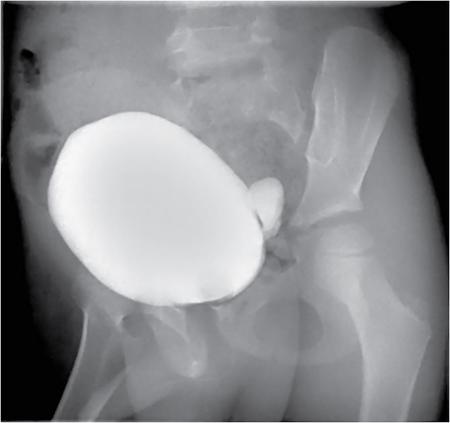

Anmol Bhatia, Kushaljit Singh Sodhi, Akshay Kumar Saxena Congenital as well as acquired anomalies of the bladder and urethra are a significant cause of morbidity in children. Various radiological investigations for imaging bladder and urethra include ultrasonography (US), voiding cystourethrography (VCUG) and intravenous urography (IVU), computed tomography (CT), magnetic resonance imaging (MRI) and contrast-enhanced voiding urosonography. In this chapter, we will discuss and illustrate a wide spectrum of congenital and acquired anomalies of bladder and urethral in children. Foetal allantoic stalk is the connection between the bladder dome and the umbilicus during the embryogenesis. Normally, it gets involuted by the second month of gestation. Depending on the degree of the persistence of this foetal allantoic stalk results in varying types of urachal remnants. The clinical presentation depends on the type of urachal remnant: Fluoroscopy is the best imaging modality for documenting the patency of urachus. However, there may be an underestimation of the exact length of the urachal remnant as inflammation occurring along the tract may block its lumen. CT and MRI are usually not needed for the detection of urachal remnants. However, urachal remnants are usually detected incidentally on CT scan done for other indications. Cystic or solid elongated tubular structure may be seen extending from bladder dome to umbilicus. A focal cystic lesion (Fig. 10.11.3) may be seen in the midline anywhere from bladder dome to umbilicus. In case the urachal remnant present with the symptoms, resection of the entire tract is warranted. Bladder diverticulum are localized outpouching from the bladder wall. They can be single or multiple of varying sizes. A male predominance is seen in comparison to females. It has been traditionally classified into four types: They can be incidentally detected or present with complications including recurrent UTI, urinary retention, incontinence, stone formation, VUR and bladder or ureteric obstruction. Bladder diverticulum should be differentiated from ‘bladder-ears’ in newborn male which is bilateral protrusion of bladder wall into inguinal ring. These are transient and disappear with growth. Appearance of diverticulum depends on cause, location, size and presence of complication features. VCUG under fluoroscopy is most efficient method to demonstrate diverticulum. Fluoroscopic monitoring during all phases including voiding and immediate postvoiding phase is important along with oblique and lateral views. Contained contrast-filled outpouching is seen which may be visible only during voiding phase when urine is forced into diverticulum during bladder contraction. Associated VUR is present in 50% of cases. Round or oval anechoic structure arising in communication with the bladder is seen. Well-defined homogenous structure with fluid attenuation/signal intensity arising from bladder wall (Fig. 10.11.6). Secondary complications like stone formation or rupture can be seen. Surgical removal using intravesical, extravesical or combined approach may be performed along with meticulous repair of bladder wall. Urinary bladder neoplasms are not commonly encountered in children. The majority of bladder neoplasms in children are of mesenchymal origin and overall rhabdomyosarcoma is the most common malignancy (Table 10.11.1). They can be incidentally detected or present with urological symptoms including dysuria, haematuria, incontinence and lower abdominal pain. It can manifest as filling defect in MCU studies done for other indications. Ultrasound is usually the first line investigation with cross-sectional imaging being performed in suspected cases for accurate characterization, localization, disease extent and complication. Histopathological analysis is often needed for final diagnosis. The differential diagnosis of bladder masses includes masses arising from adjacent pelvic structures, variants like ureterocoele or urachal remanent, mass forming cystitis (eosinophilic cystitis, BK virus–associated cystitis), haematoma, calculi or iatrogenic materials (e.g. Deflux used in VUR surgeries). Rhabdomyosarcoma Leiomyoma Neurofibroma IMT Leiomyosarcoma Angiosarcoma Haemangioma Urothelial carcinoma PUNLMP: urothelial papilloma Fibroepithelial polyp Paraganglioma Nephrogenic adenoma PUNLMP, papillary urothelial neoplasm of low malignant potential. Rhabdomyosarcomas are the most common urinary bladder neoplasms in first two decades of life presenting typically at ages 2–6 years and 15–19 years. Syndromic association with Li–Fraumeni cancer syndrome, NF type 1, MEN 2A has been found; however, majority are sporadic in origin. Histological subtypes include embryonal rhabdomyosarcoma (classical, botryoid and spindle cell variant), alveolar and undifferentiated sarcoma types of which embryonal form accounts for 90% of all cases. Locoregional spread to adjacent organs, muscles, regional lymphnodes is seen with distal metastasis to lung, cortical bones and retroperitoneal lymphnodes. Metastasis is found in approximately 10%–20% of patients at time of initial presentation. Overall survival and outcome depend on patient age and histological subtype with patients between 1–9 years of age and embryonal subtype having a better prognosis. Imaging work-up includes CT or MRI pelvis for local disease characterization and extent, CT chest, bone scintigraphy or FDG-PET for metastasis and staging. They commonly arise from bladder trigone and neck area. Ultrasound: They are typically large, intraluminal, multilobulated masses with well-defined margins and homogenous hypoechoic or hyperechoic echotexture. Foci of necrosis or haemorrhage are often seen. Vascularity on colour Doppler is increased. Hydronephrosis and bladder neck obstruction secondary to mass can be found. CT: Bulky heterogenous low attenuation mass that may invade into periurethral or perivesical tissue (Fig. 10.11.7). Calcification is rare.